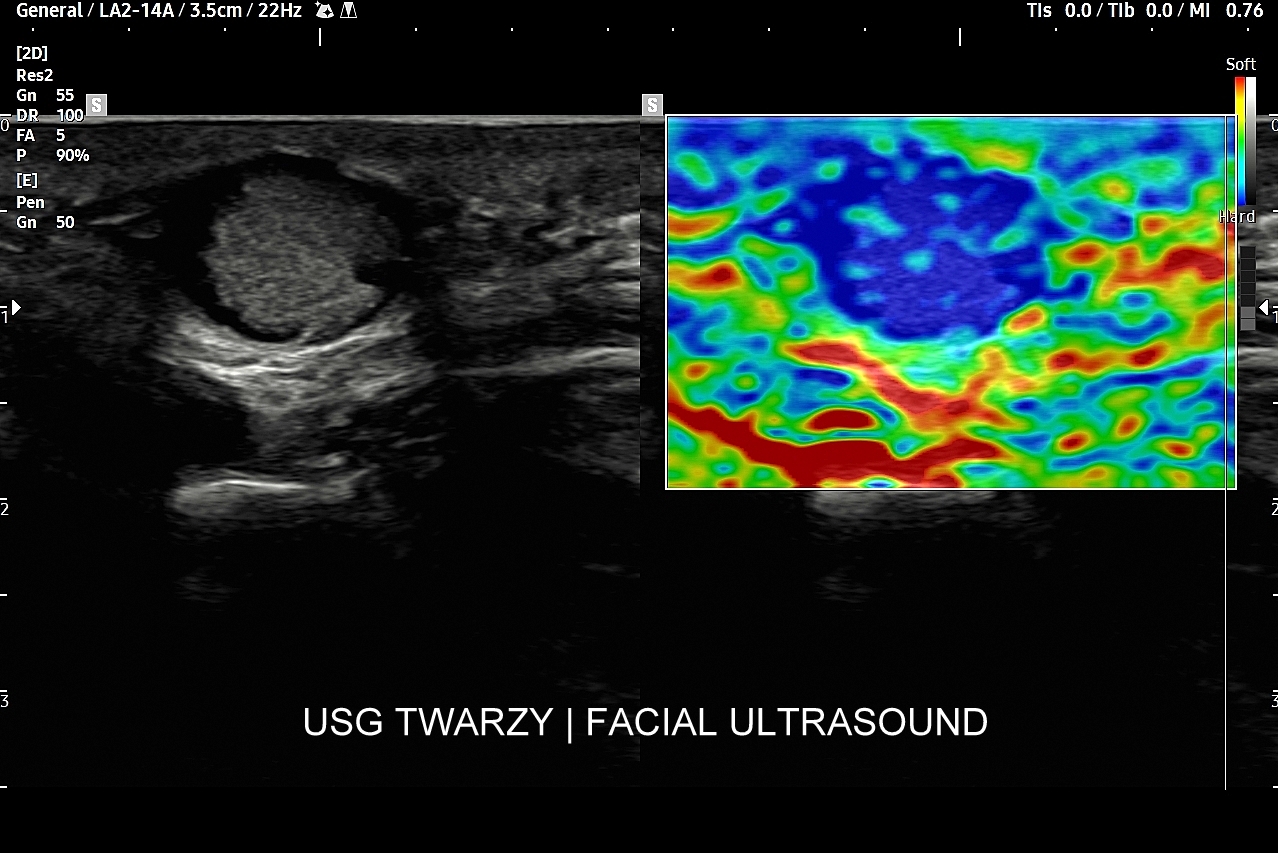

USG twarzy

Badanie USG twarzy, często nie do końca fortunnie zwane USG skóry twarzy, to stosunkowo nowa metoda diagnostyczna wprowadzona we Wrocławiu do użytku przez dr Tomasza Szczepańskiego, a wykonywana w przypadku schorzeń z zakresu medycyny estetycznej, dermatologii, laryngologii, stomatologii i chirurgii. Wśród rozpoznań w badaniu USG skóry twarzy dominują choroby infekcyjne takie jak rozprzestrzeniające się w tkankach miękkich zapalenia i ropowice pochodzące od zapaleń zębów czy migdałków, powikłania ropne w przebiegu trądziku pospolitego lub różowatego, po iniekcjach wypełniaczy i po innych zabiegach z zakresu medycyny estetycznej. Kolejną dużą grupą patologii skóry twarzy są torbiele inkluzyjne, których przykładem są kaszaki, oraz guzy twarzy, wśród których dominują ziarniniaki jako odległe acz częste powikłanie depozycji wypełniaczy z kwasu hialuronowego.

USG twarzy wykorzystywane jest także do diagnozowania urazów twarzoczaszki, zarówno w obrębie tkanek miękkich (np. uraz zmiażdżeniowy tkanki podskórnej), jak i kości (np. złamanie kości jarzmowej, kości nosa); do oceny zaawansowania bruksizmu; oceny i kategoryzowania naczyniaków twarzoczaszki; diagnozowania zapaleń tętnic skroniowych; czy powikłań naczyniowych w medycynie estetycznej. Badanie USG twarzy służy również do oceny defektów kosmetycznych zarówno przed ewentualnymi zabiegami estetycznymi i plastycznymi, jak i po nich.